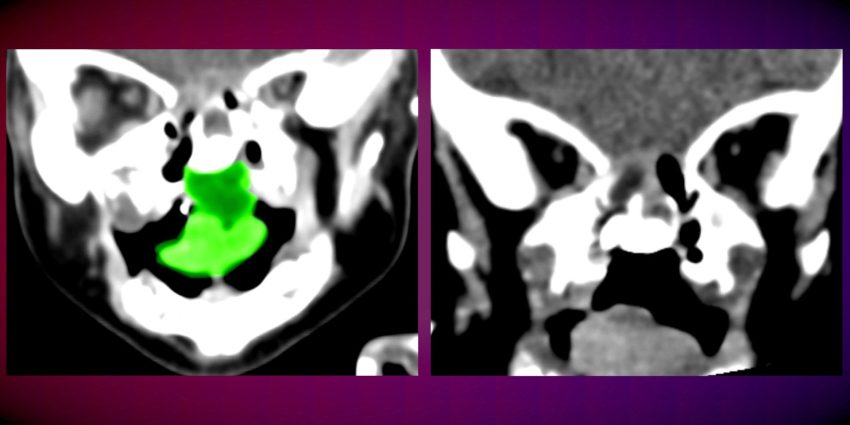

צילומי C.T של הפעוטה לפני (משמאל) ואחרי הניתוח. במרכז התמונה הימנית – החלל שנותר לאחר הסרת הגידול (צילום: דוברות הקריה הרפואית רמב"ם)